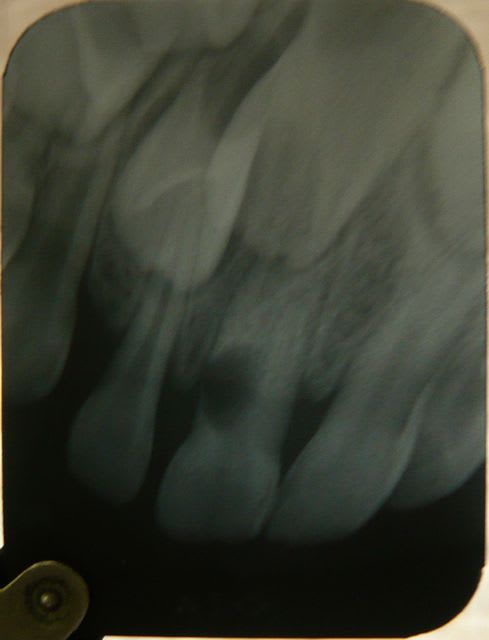

Je réactive ce message avec mon patient vu à 4 mois de la consultation précédente du mois d'aout:

J'avais fait deux séances d'hydroxyde de calcium en août et j'ai obturé sans pression avec un IRM. Il y avait une communication endo-parodontale juste sous le collet en vestibulo distal au départ) visualisée en soufflant légèrement avec la seringue à air.

Voici le résultat en image à 4 mois exactement. Aucune douleur, pas de mobilité dentaire.

sinon, à 6 mois on a certes une guérison clinique, mais radiologiquement on a plutôt le contraire d'une amélioration.

contrôle radio dans 3 mois, si ça continue à évoluer, extraction, à 5 ans et demi socialement acceptable.

Pour l'aggravation au niveau radiologique je n'en suis pas sûr mais il est vrai que l'aspect plus dense de l'hydroxyde de calcium que j'avais posé à complètement disparu pour laisser place à une vacuité radiologiquement visible qui ne me convient pas trop mais bon...

Avoir une obturation parfaitement étanche jusqu'au 2/3 de la racine me semble très compliqué à obtenir avec en plus une communication endo-paro latérale 3mm sous le collet.